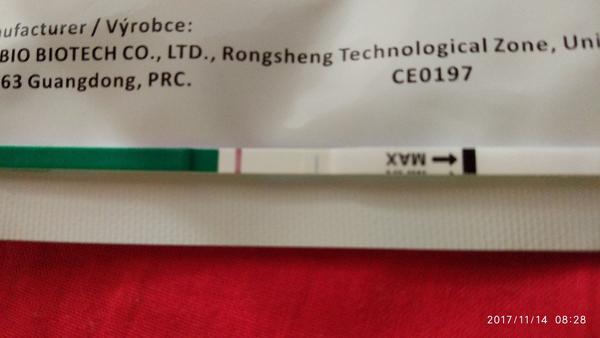

@prskavka2223 Tvoj test z 12.11...Ak maju byt // blizko seba, tak vidim dusika...Pozri trosku som test upravila...Ty si tam nazivo nieco videla? ...Testovala si od tohto testu, ci nie este?